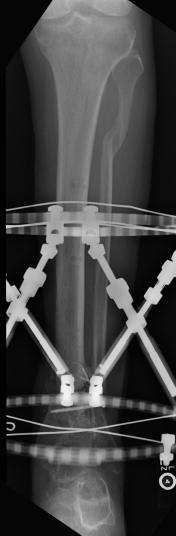

Postoperative (15th) images of left ankle

On May 30th 2007 exactly 2 years and 2 days from the day that Liam had his skydiving accident, doctor Ott removed the lower part of Liam’s left

leg using what is described as an Ertl procedure. The Ertl procedure results in a residual limb that is stronger and has a greater ability to load bear.

It is expected that Liam’s fatigue will be greatly reduced as a result of the Ertl procedure. The X-Rays show the best details associated with the Ertl

procedure. It can clearly be seen that a piece of bone (from the fibula) has been used to bridge the gap between tibia and fibula. What can not be seen

is the amount of tissue and muscle that was used (found normally in the lower part of the limb) to form a sort of pocket surrounding the remaining bone.

Through the great efforts of doctor Ott and Owen from the Artificial Limb Specialist Group, Liam has been given good responses regarding his rate of

healing and his prognosis for a great recovering. At this stage Liam is using sleeves that help reduce swelling and shape the stump so that it best fits the

prosthetic limb that will be used by Liam to walk.